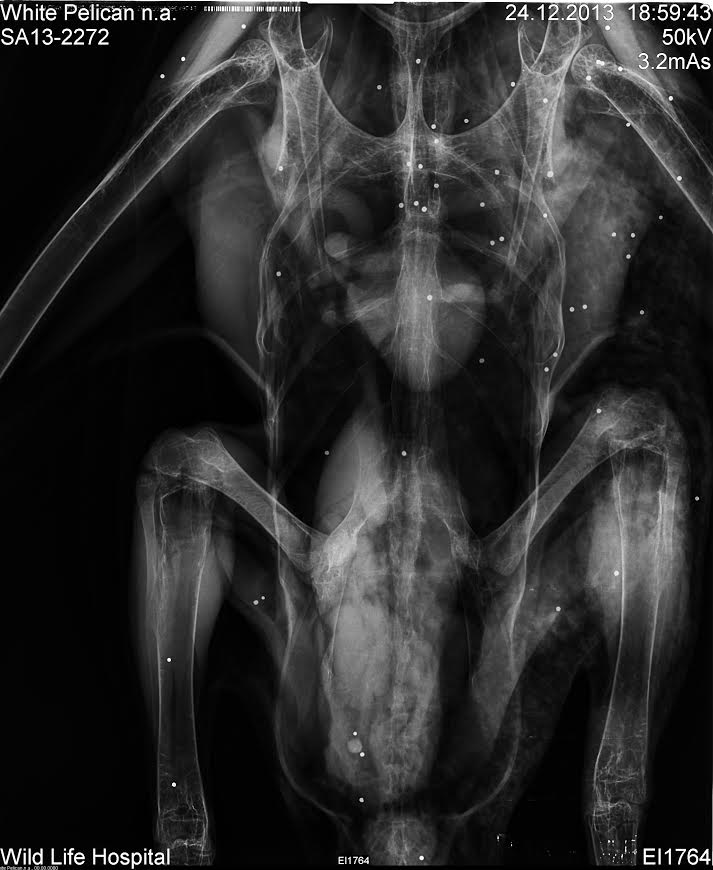

היה ברור שמדובר בפגיעות ירי אולם רק כאשר פוענחו צילומי הרנטגן שלו, הבינו המטפלים את גודל הזוועה.

בתוך גופו של השקנאי נספרו 110 כדוריות עופרת.